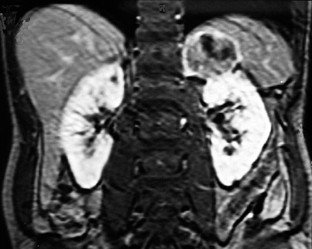

Background. A 57-year-old African American man presented to a tertiary care center with a 6-month history of fatigue and worsening abdominal pain. He had lost 9.1 kg in weight in the 3 months leading up to presentation, and described subjective fevers and night sweats for 1 month with a nonproductive cough and blurred vision for several weeks before presentation. He had chronic renal insufficiency, sleep apnea, hypertension, and peripheral vascular disease.

Investigations. Physical examination, complete blood count, peripheral blood smear, leukocyte alkaline phosphatase score, bone marrow biopsy, CT of the chest, abdomen, and pelvis, MRI of the abdomen and pelvis, measurement of plasma and urine metanephrines, 24 h urine testing for cortisol and 17-ketosteroids, measurement of serum granulocyte colony-stimulating factor (G-CSF) level, histopathologic examination and immunohistochemical staining of resected tumor.

Diagnosis. G-CSF-secreting adrenal carcinoma with rhabdoid-like differentiation.

Management. En bloc surgical resection of kidney, suprarenal mass and spleen was performed, followed by initiation of mitotane chemotherapy 3 months later.